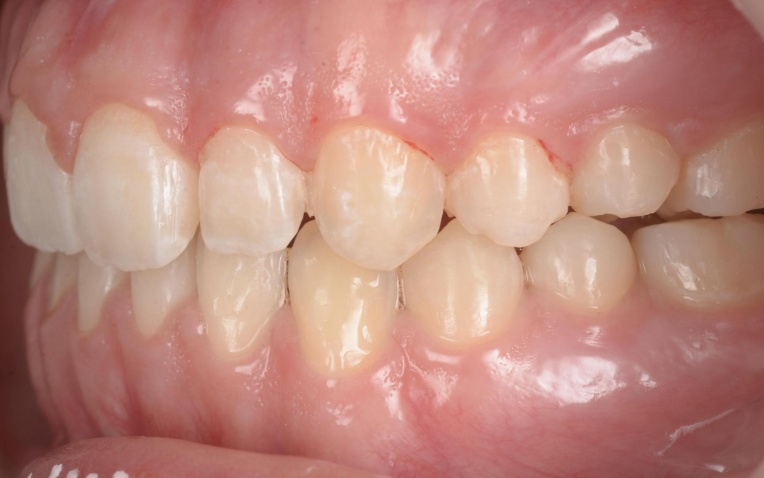

「前歯が噛み合わないので治したい」とご相談いただきました。 |

拝見したところ、重度の開咬(かいこう)が認められました。 |